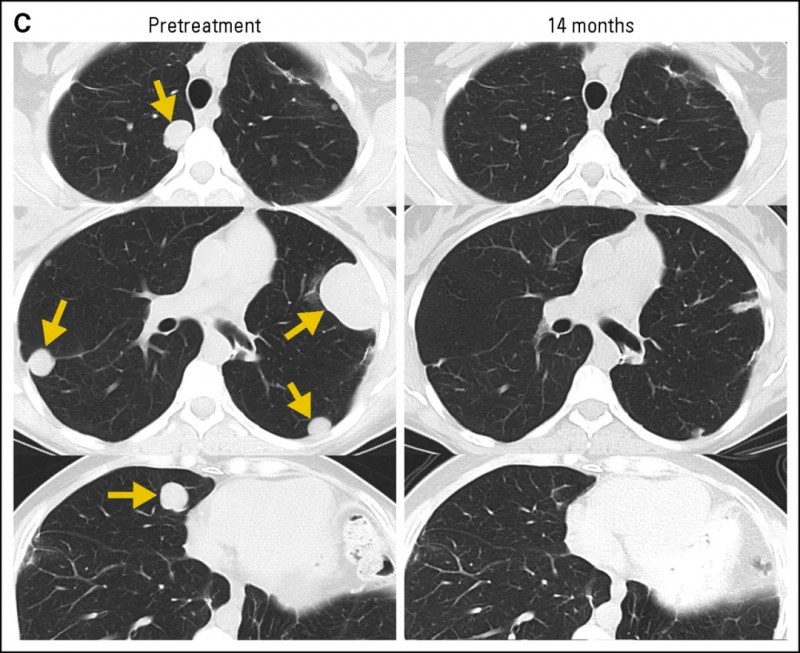

3、13号滑膜肉瘤患者:经两次NY-ESO-1TCR转导T细胞治疗后,多发性肺转移病灶消退,部分缓解(PR)持续长达18个月(详见下图C)。

▲图源“J Clin Oncol ”,版权归原作者所有,如无意中侵犯了知识产权,请联系我们删除